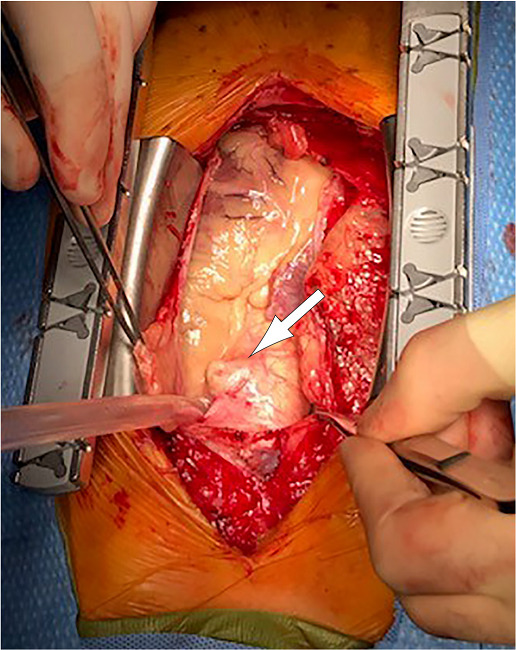

Following median sternotomy, significant outpouching of ascending aorta was visualized (Figure 2). Heparin administration and cardiopulmonary bypass were initiated, and systemic temperature was cooled to 32°C. Cardioplegic arrest was achieved utilizing 1800 mL of cold blood cardioplegia and an intramyocardial temperature of 15°C. During aortic cross-clamping, retrograde blood cardioplegia was administered every 10-15 minutes.

This case illustrates two important aspects of this disease process. First, the rarity of combined IMH and penetrating aorta in AAS, and second, the photographic depiction of an advanced case of an exfoliating penetrating ulcer with imminent rupture. This case also highlights the emergent nature of this relatively rare subset of AAS that is often underappreciated and undertreated.